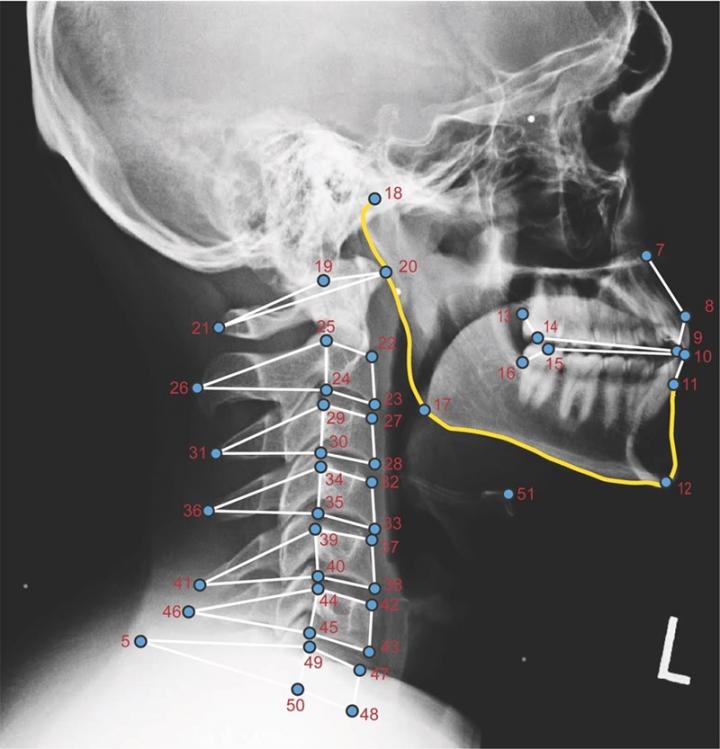

image: Figure demonstrating where landmarks were placed on the head/neck so that a geometric morphometric analysis could be completed.

The study looked at neck and jaw postures when using handheld electronic devices, the results suggesting that women and shorter individuals bend their necks differently than men and taller individuals; this could be related to the higher incidence of neck and jaw pain experienced by women.

As ownership of electronic handheld devices increases in the United States, new information is needed about how posture may affect the neck and jaw joint when using these devices. Some evidence shows that using these devices, such as cells phones or tablets, in certain postures may influence both the neck and jaw, eventually causing the development of pain in both. The study asked participants to hold and use electronic devices in five different postures while an X-ray was taken. These postures ranged from a neutral position of sitting straight up to a fully reclined position, as if the participant were leaning back in a chair.